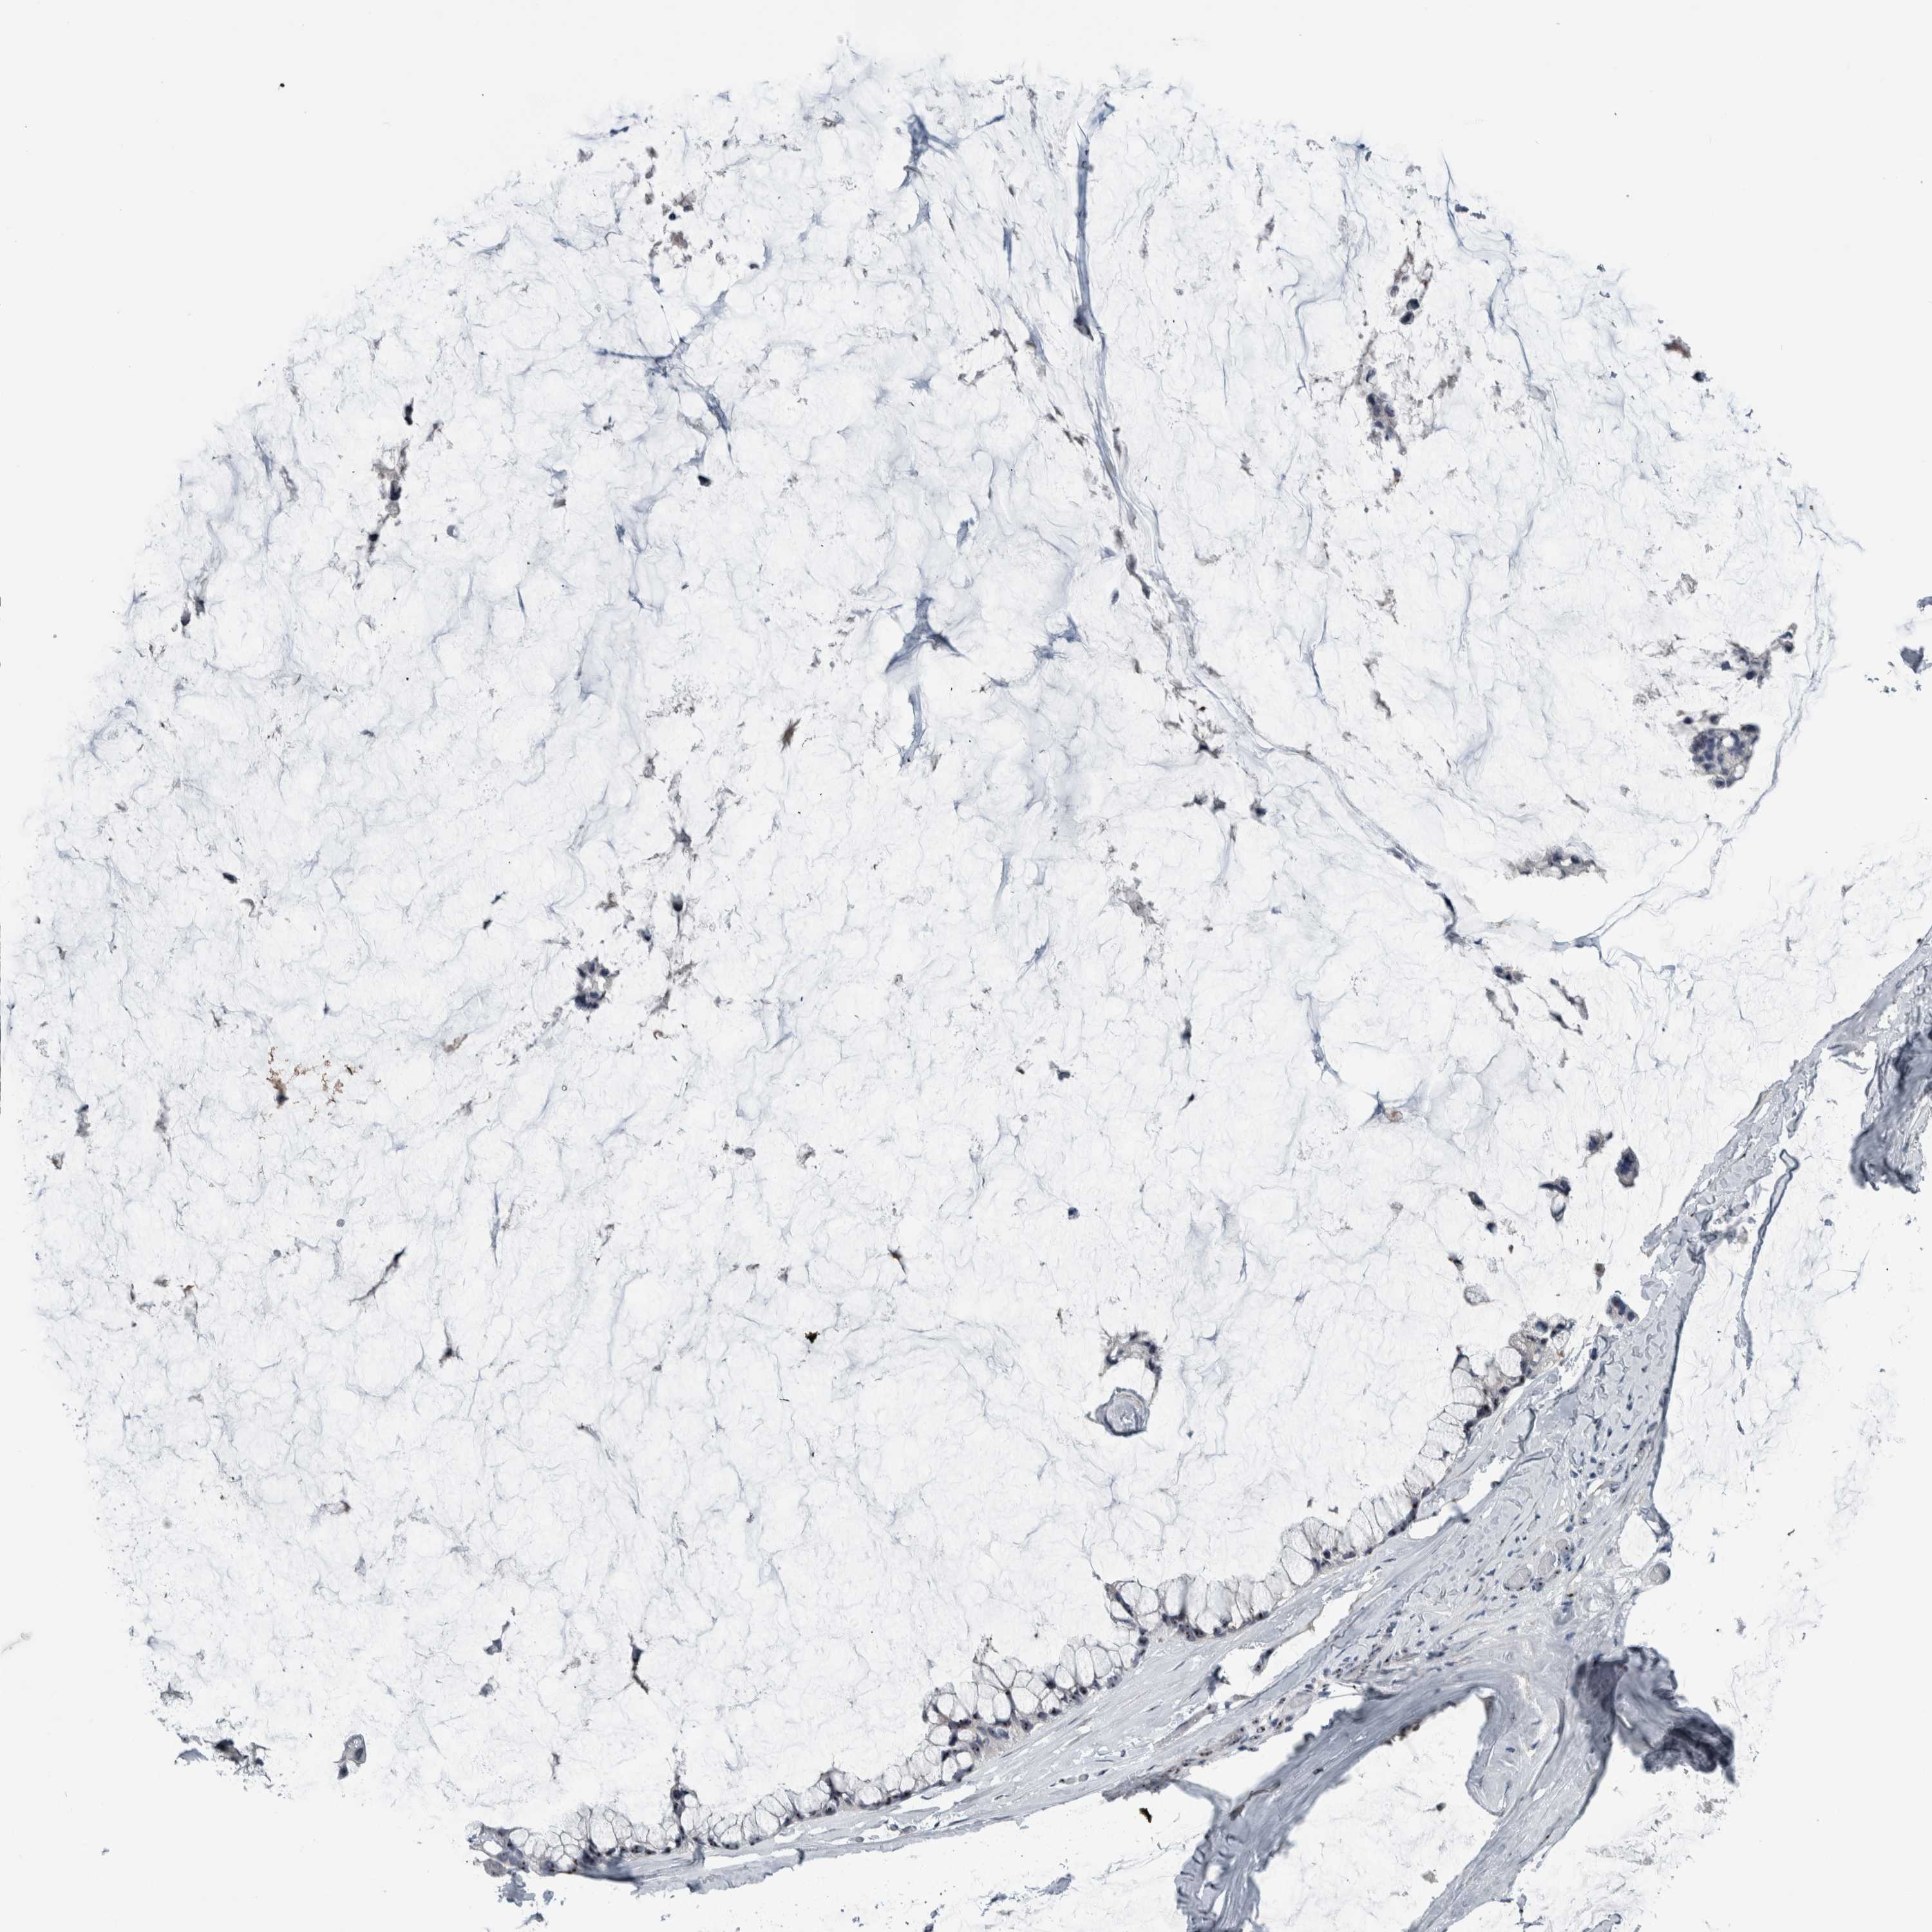

OVARIAN CANCER - Protein expressioni

A mouse-over function shows sample information and annotation data. Click on an image to view it in a full screen mode. Samples can be filtered based on level of antibody staining by selecting one or several of the following categories: high, medium, low and not detected. The assay and annotation is described here.

Note that samples used for immunohistochemistry by the Human Protein Atlas do not correspond to samples in the TCGA dataset.

Antibody stainingi

Antibody staining in the annotated cell types in the current human tissue is reported as not detected, low, medium, or high, based on conventional immunohistochemistry profiling in selected tissues. This score is based on the combination of the staining intensity and fraction of stained cells.

Each image is clickable and will lead to virtual microscopy that enables deeper exploration of all samples and also displays staining intensity scores, fraction scores and subcellular localization as well as patient and tissue information for each sample.

Antibody HPA025936

Staining

High

Medium

Low

Not detected

Intensity

Strong

Moderate

Weak

Negative

Quantity

>75%

75%-25%

<25%

None

Location

Nuclear

Cytoplasmic/membranous

Cytoplasmic/membranous,nuclear

Cystadenocarcinoma, serous, NOS

Carcinoma, endometroid

Cystadenocarcinoma, mucinous, NOS

Carcinoma, NOS